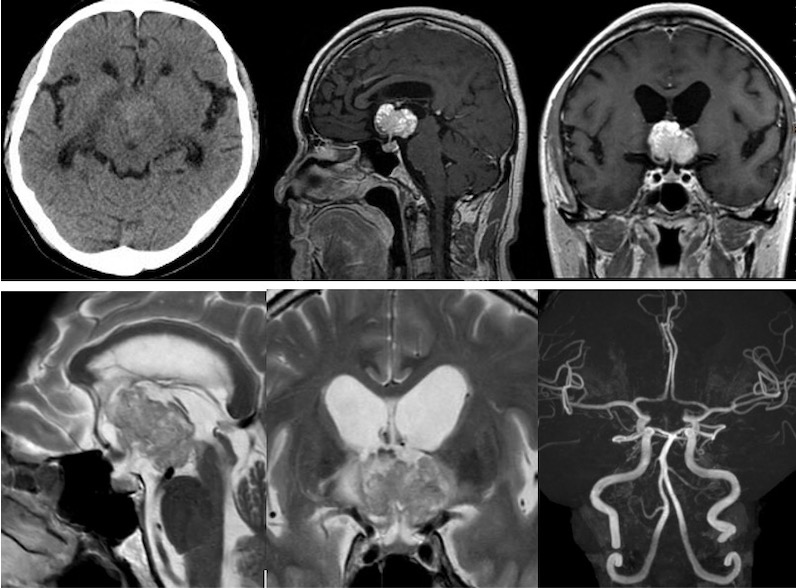

視力障害、記銘力障害で発症した頭蓋咽頭腫を両側前頭開頭、anterior interhemispheric approachで切除しました。トルコ鞍部や鞍上部にはほとんど局在しないためtranslamina-terminalis approachを選択しました。視床下部動脈を温存し、内減圧を繰り返し、焼き鳥テクニックとリングキュレットで狭い術野から腫瘍を起こして摘出しました。術後年齢が比較的若かったためかすぐに覚醒しました。

Trans-lamina terminalis approach、何度もやった古典的なアプローチです。A2と伴奏し縦走する視床下部動脈を温存して、その間隙から腫瘍を減圧していきます。

腫瘍を減圧し、最後に起こして、中脳水道や脳底動脈を確認しました。視交差の下は減圧にとどめました。